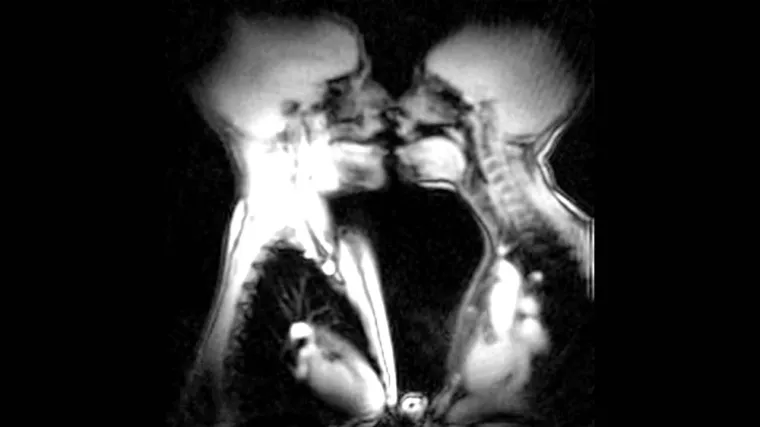

Buzzara se igra doktora: Ove slike MR-a i rendgena će vam pokazati kako zapravo izgleda naša unutrašnjost

Ukoliko Vas je ikada interesiralo kako izgleda unutrašnjost naših prstiju, kako izgleda unutrašnjost abdominalnog područja osobe koja pokušava prošvercati ilegalne 'tvari' i supstance, ili, pak, ako Vas je ikada interesiralo kako izgledaju zubi sedmogodišnjaka, a kako tridesetogodišnjaka, kliknite 'SLJEDEĆA':